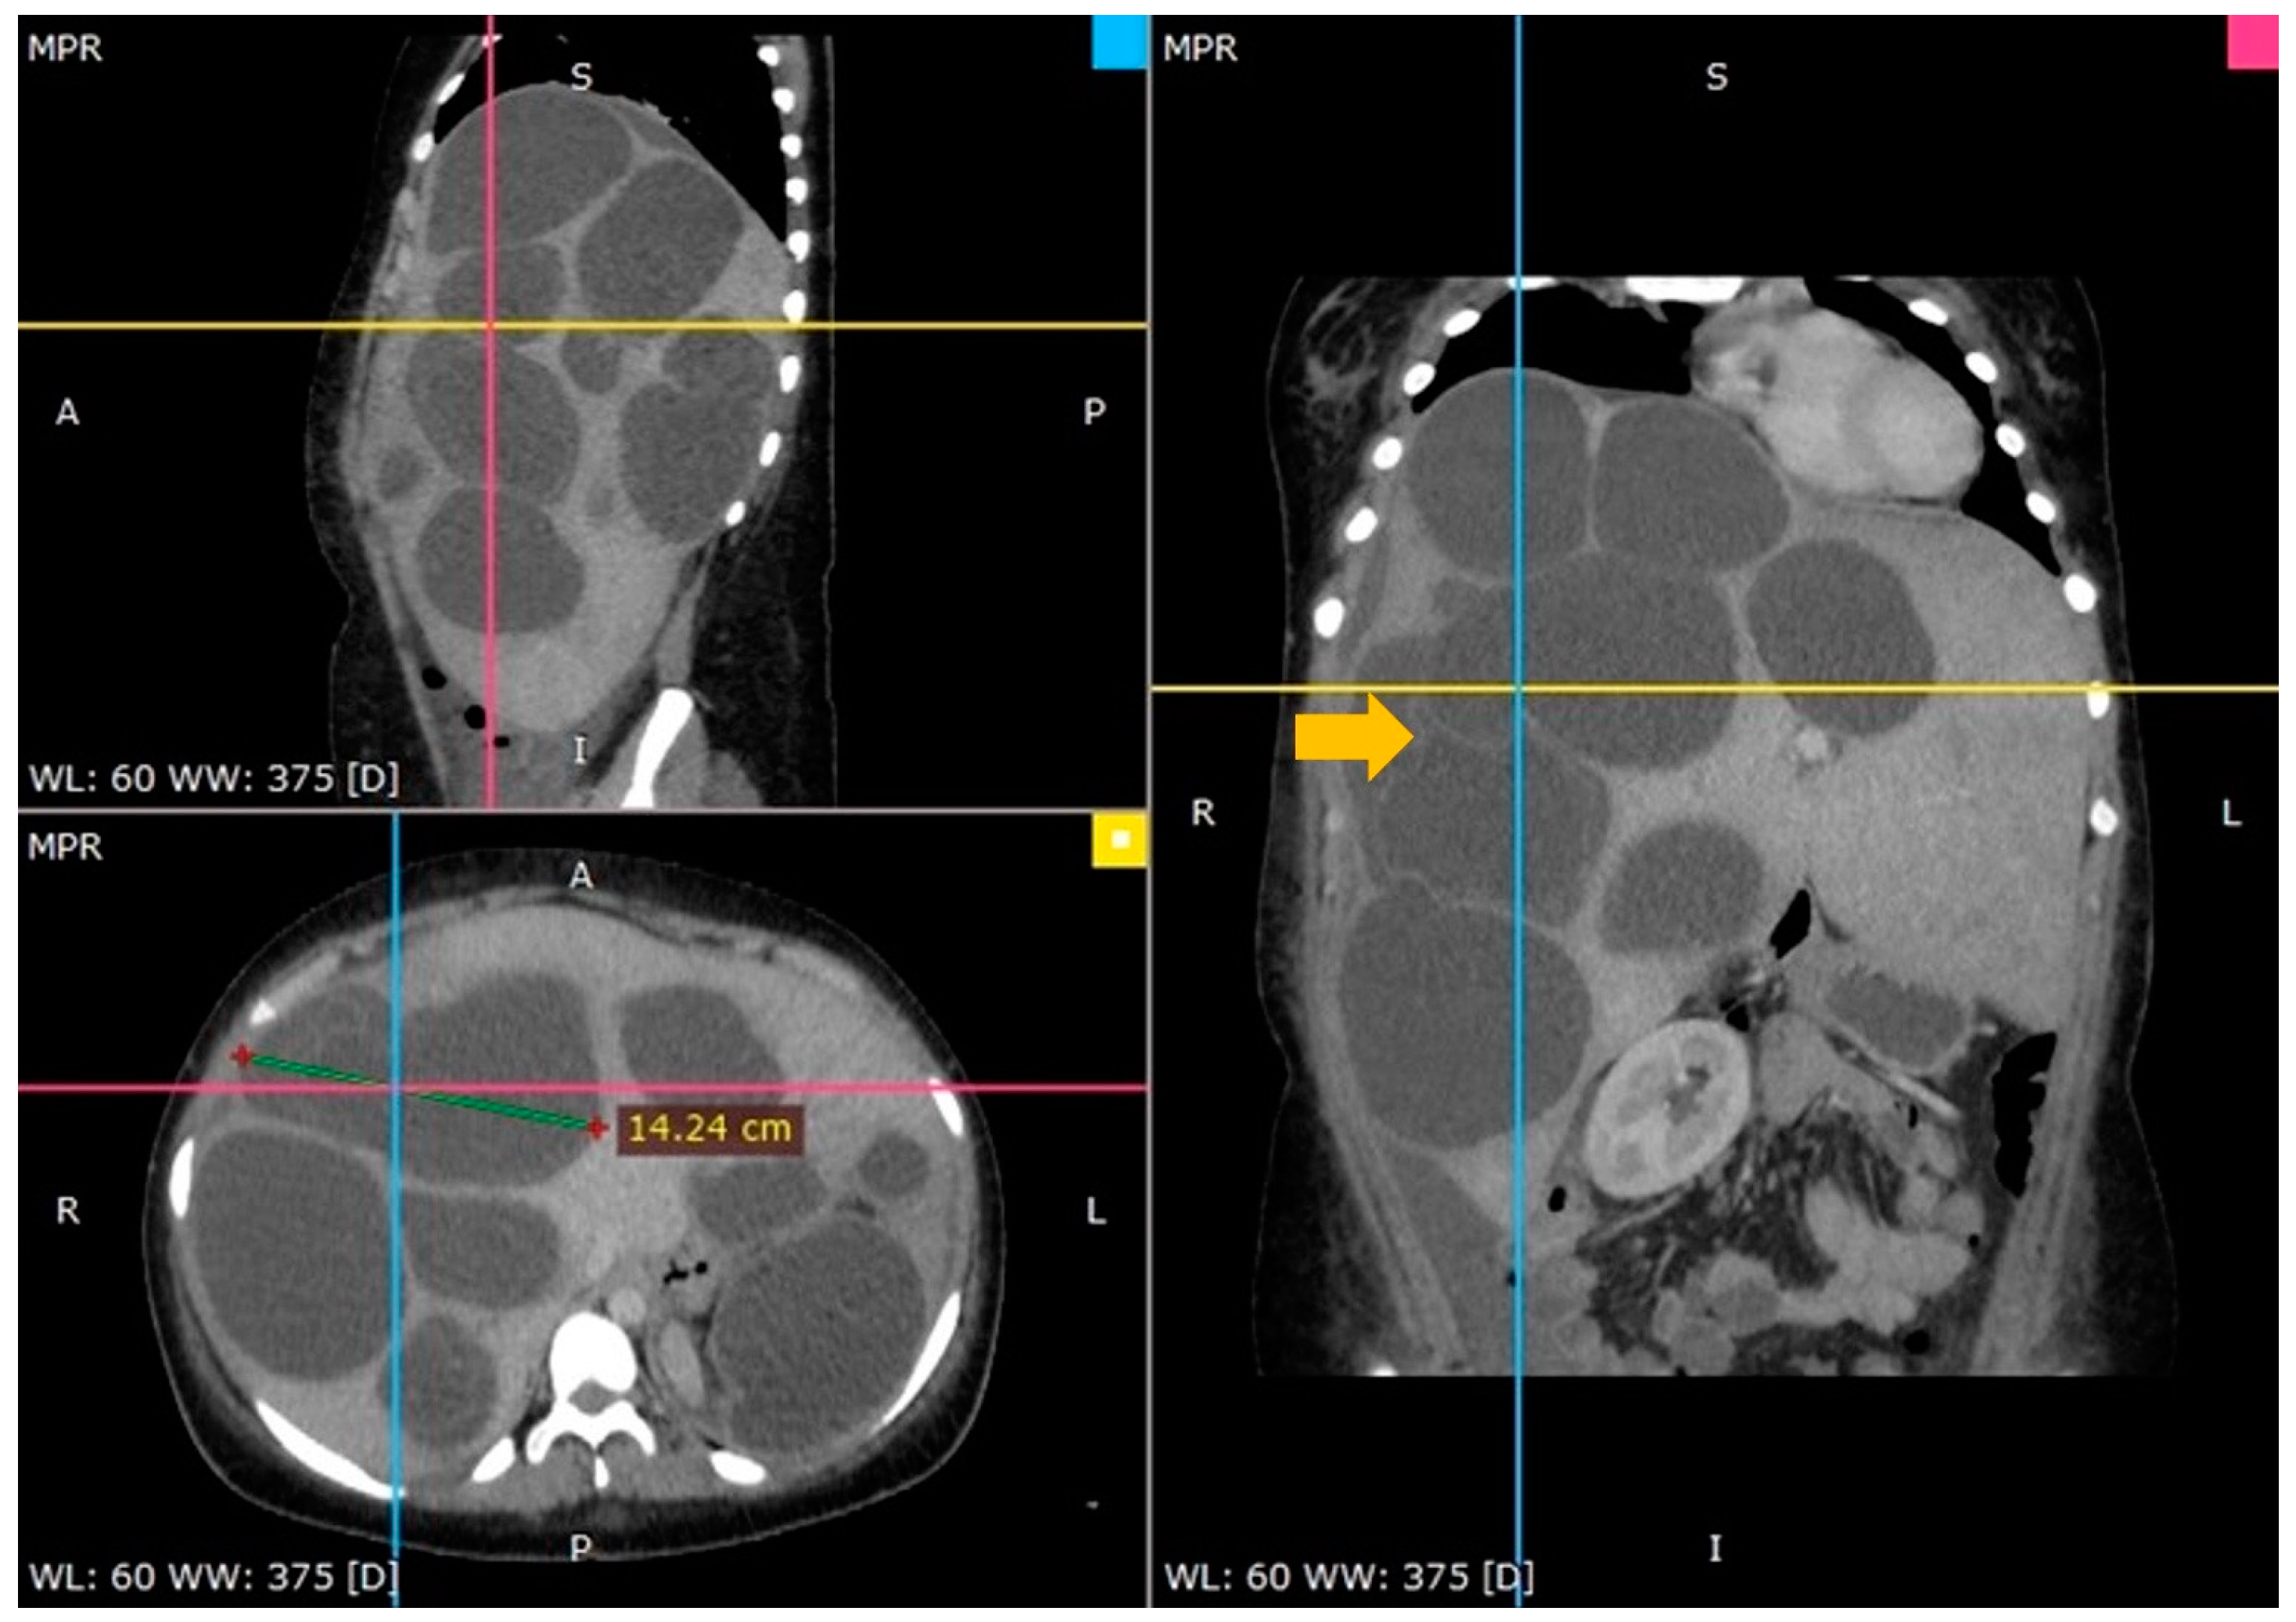

3.1. Case 1